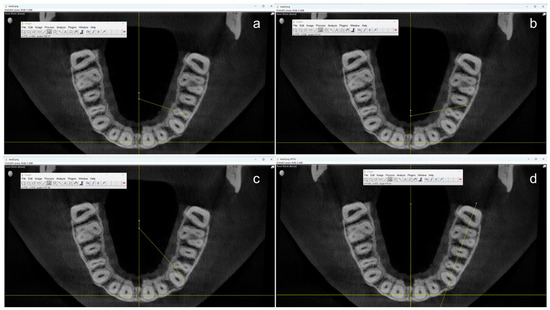

In the next step, the multiplanar reconstruction was used to identify axial planes in which the root canals were clearly visible. The centerline of the maxilla was marked and the coronal screenshot was taken just apically of the pulpal floor. The apical screenshot was taken in the most apical plane where the root(s) were recognizable.

All measurements were performed by one single operator using the open-source software ImageJ (OpenSource, Version 1.54f) starting from the centerline to ensure a uniform reference position (Figure 2).

First, the angle at which the two root canals of the maxillary first premolars overlap was measured by drawing a line through the center of these canals. Two additional angles were measured to determine the angle at which the neighboring teeth would start to overlap the first premolar. On the one hand, the angle between the distal contour of the adjoining canine and the mesiopalatal contour of the first premolar. On the other hand, the angle between the distal root contour of the first premolar and the mesial root contour of the second premolar. If a root canal was not clearly visible in the apical section, the center of the root contour was used as an orientation aid. Teeth with root canal fillings, root resorptions, atypical anatomy (e.g., more than two roots), and CBCT artifacts to the extent that made valid measurements impossible were not taken into account for this study.